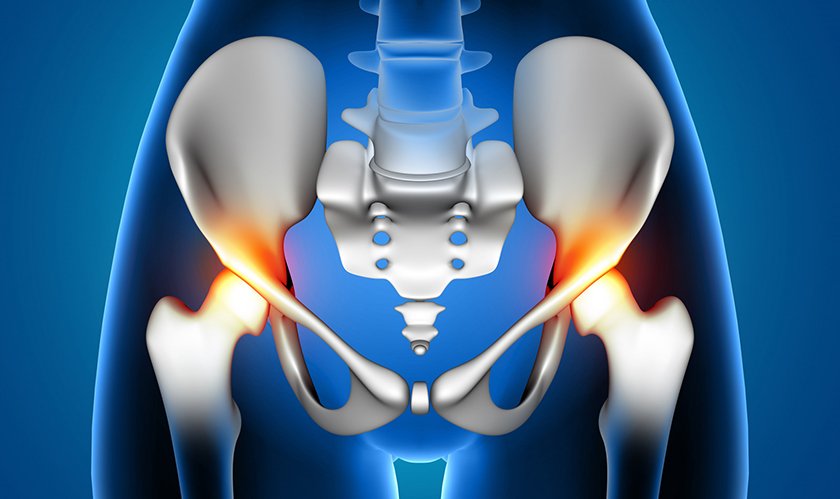

Who Needs Total Hip Replacement?

You may be a candidate for total hip replacement if you experience:

Persistent hip pain affecting daily activities

Difficulty walking, sitting, or bending

Hip stiffness or reduced range of motion

Pain that continues despite medication, physiotherapy, or injections

Hip joint damage due to arthritis, injury, or avascular necrosis